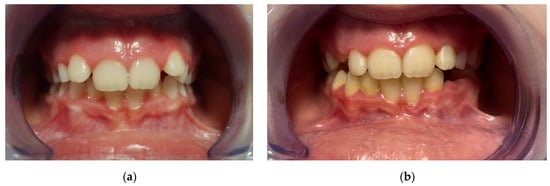

All subjects presented have reported excellent compliance with the AMCOP device. A common issue was excessive salivation, this effect, however, gradually decreased after a few days. One of the potential advantages of an EA over functional appliances is that they are well accepted by children since they do not require dental impressions, and they are asked to wear the appliance only at night and for a few hours in the afternoon. Furthermore, due to its lower cost compared to treatment with a functional appliance, interceptive therapy with an EA could be an important alternative for treating subjects with difficult financial conditions (Figure 3).

Figure 3. Intraoral frontal photographs of one of the included subjects treated with AMCOP device. (a) pre-treatment (T0), (b) post-treatment (T1).